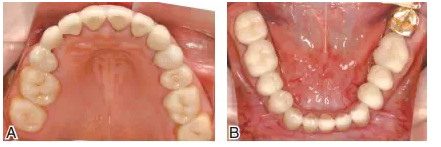

圖17雙側上頜后牙采用全瓷嵌體(CAD/CAM,eMax,Vivodent Ivoclar),其他基牙采用金合金烤瓷冠修復。A上頜后牙的高嵌體基牙預備;B后牙的工作模型;C后牙全瓷高嵌體粘接中,氫氟酸酸蝕,樹脂粘接水門汀粘固

圖18修復完成后的上下頜咬合面觀